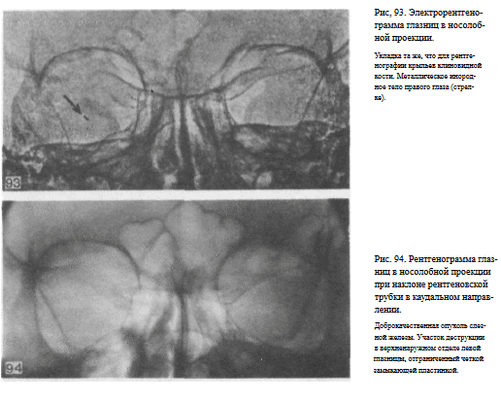

СНИМОК ГЛАЗНИЦЫ В НОСОЛОБНОЙ ПРОЕКЦИИ

Назначение снимка — изучение контуров костей, образующих вход в глазницу, структуры верхней и наружной ее стенок, ширины и контуров верхних глазничных щелей, а также выявление инородных тел в полости глазницы.

В качестве примера информативности снимка глазниц в носолобной проекции для выявления инородных тел глаза и деструктивных изменений стенок приводим два наблюдения.

Одно из них — случай ранения глаза металлической стружкой (рис. 93), другое — случай деструкции верхненаружного края глазницы при доброкачественной опухоли слезной железы (рис. 94).